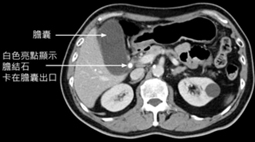

然而,大多數有膽結石的人終其一生都不會症狀,只有在膽結石剛好卡在膽囊出口時才會出現腹痛症狀。此時,若膽結石可自行掉回膽囊內,患者腹痛的狀況就可能得以緩解,若患者反覆發作或連續疼痛超過數小時無法獲得緩解,通常就需要就醫。

膽結石卡在膽囊出口影像圖片